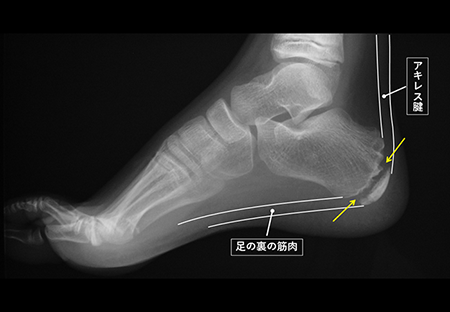

発育期の子どもの骨は、大人と違い、骨が成長していく部分(骨端線あるいは成長軟骨と言います)が残っています。(下図の矢印)

骨端線は物理的に弱く、かかと部分の骨(踵骨)には、アキレス腱と足の裏の筋肉がついているため、運動で繰り返し骨端線の周囲にひっぱる力が加わることで、炎症を起こしたり、骨に細かい傷がついたりすることが痛みの原因と言われています。

レントゲン検査で、骨端線よりも外側の部分の骨(骨端核)が他の部分にくらべて白くなっていたり(骨硬化)、いくつかの骨に分かれていたりする(分節化)などの変形があるか等を確認します。